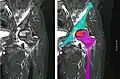

X-ray images of avascular necrosis in the early stages usually appear normal. In later stages it appears relatively more radio-opaque due to the nearby living bone becoming resorbed secondary to reactive hyperemia.[2] The necrotic bone itself does not show increased radiographic opacity, as dead bone cannot undergo bone resorption which is carried out by living osteoclasts.[2] Late radiographic signs also include a radiolucency area following the collapse of subchondral bone (crescent sign) and ringed regions of radiodensity resulting from saponification and calcification of marrow fat following medullary infarcts.

Radiography of avascular necrosis of left femoral head. Man of 45 years with AIDS. -

Nuclear magnetic resonance of avascular necrosis of left femoral head. Man of 45 years with AIDS. -